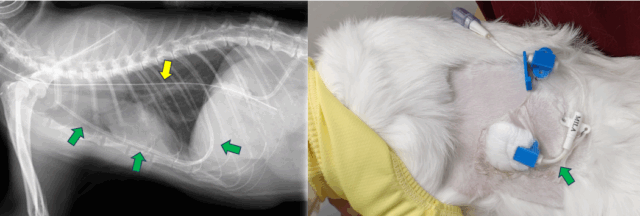

数日前から「元気がない」「食欲がない」「呼吸が苦しそう」といった症状が見られる猫ちゃんが来院されました。画像検査の結果、胸の中に水が溜まる「胸水貯留」が確認されました。

下の画像は、左が健康な猫ちゃん、右が今回の猫ちゃんのレントゲンです。

胸全体が白く写っており、🟦青い矢印が示すように、肺が十分に膨らんでいないことが分かります。

これは胸水が大量に溜まっている状態です。

胸に針を刺して胸水を採取したところ、黄色く濁った液体が出てきました。細菌も検出されたため、「膿胸」と診断されました。

胸の中に細いチューブ(胸腔ドレーン)を入れ、定期的に膿を抜き取ります。さらに、洗浄液で胸腔内を洗い流す「胸腔内洗浄」を繰り返し行い、細菌と膿を除去します。

🟩緑矢印:胸腔ドレーン

🟨黄色矢印:食道チューブ(栄養補給用)